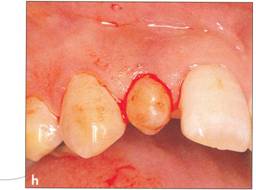

Fi 545e45f gs 5.7h and 5-7i After transplantation of the donor tooth. |

|

Fi 545e45f g 5.7j Two weeks after transplantation. The root canal has been cleaned and filled with calcium hydroxide. |